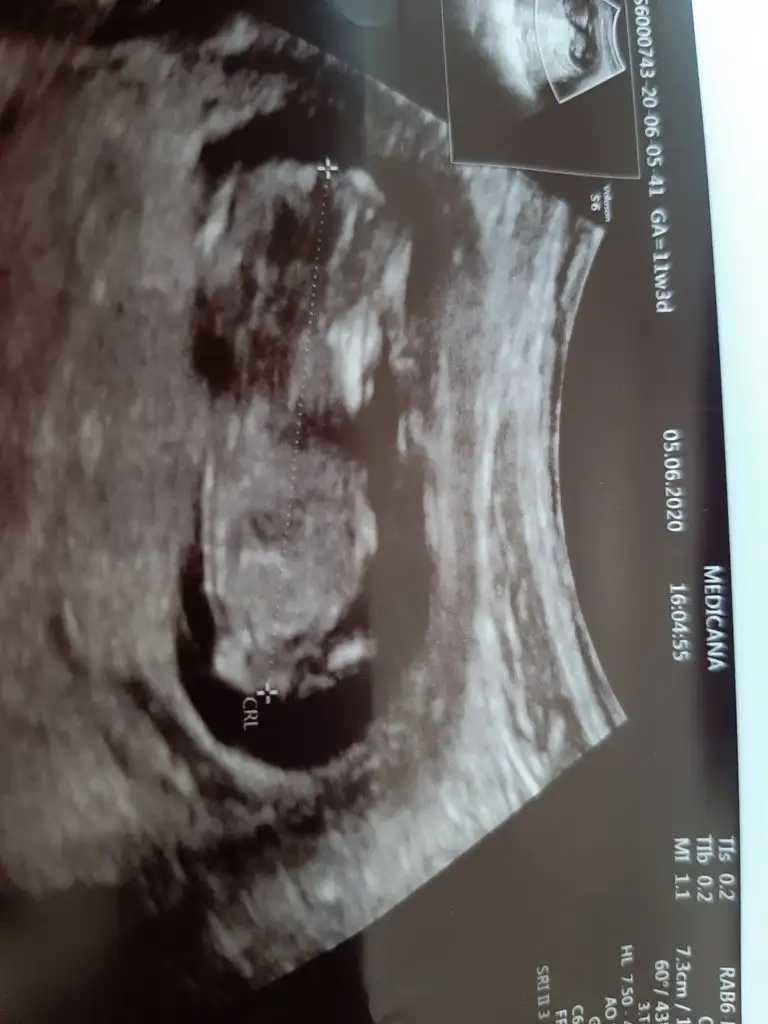

Cinsiyet tahmini

Usg